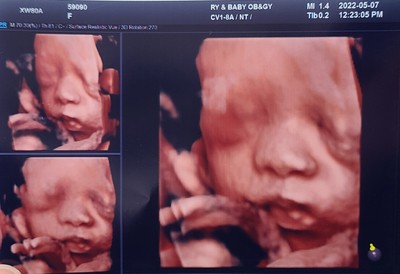

베이비페이스 후기:) 현재 모습과 비교샷

임신을 하면 나도 늘 해봐야지하며생각했었던 베이비페이스! 생각보다 가격이 나가서 고민했었는데 갈...